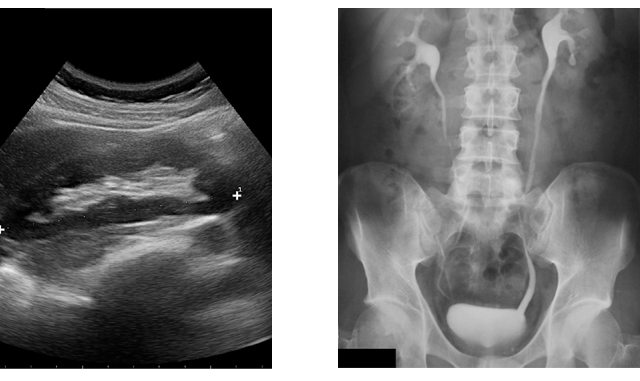

½ÅÀåÁúȯ

½ÅÀåÀÇ Áúȯ°ú ¿ä·Î°èÀÇ ÁúȯÀ» °¡Áö°í Àִ ȯÀÚµéÀº ÁÖ·Î ±Þ¹Ú´¢, ºó´¢, ¹è´¢Àå¾Ö µîÀ» È£¼ÒÇϰí Ç÷´¢, ´Ü¹é´¢, ºÎÁ¾, °íÇ÷¾Ð, ´ç´¢º´, ÀüÇØÁúÀÌ»ó, ¹ß¿ µîÀ» µ¿¹ÝÇÏ´Â °æ¿ì°¡ ¸¹½À´Ï´Ù. ÃÖ±Ù °íÇ÷¾Ð°ú ´ç´¢ ȯÀÚ°¡ Áõ°¡ Ãß¼¼À̰í, À̵é ÁúȯÀÇ ÇÕº´ÁõÀÎ ½ÅÀå±â´ÉÀÇ °¨¼Òµµ Áõ°¡ Ãß¼¼ÀÔ´Ï´Ù. ¶ÇÇÑ ÀæÀº ÁøÅëÁ¦ÀÇ ³²¿ëÀ̳ª CT Á¶¿µÁ¦ µîµµ ½Å±â´É ¾ÇÈ¿¡ ¿µÇâÀ» ÁÝ´Ï´Ù.